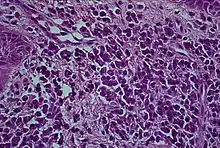

Histologically plasma cell gingivitis shows mainly plasma cells.[2] The differential diagnosis is with acute leukemia and multiple myeloma.[4] Hence, blood tests are often involved in ruling out other conditions.[3] A biopsy is usually taken, and allergy testing may also be used. The histopathologic appearance is characterized by diffuse, sub-epithelial plasma cell inflammatory infiltration into the connective tissue.[3] The epithelium shows spongiosis.[6] Some consider that plasmoacanthoma (solitary plasma cell tumor) is part of the same spectrum of disease as plasma cell cheilitis.[5]